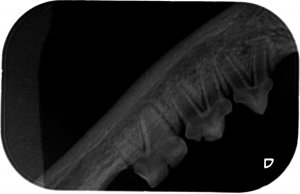

Ich hab zwar hier schon einige röntgenzahnbilder gesehen wo von Knochenabbau die rede war, deswegen hatte ich die Stellen markiert wo es (für mich ) auch so aussah, aber wahrscheinlich ist das in Ordnung so. Ich hoffe ja dass sich dazu noch jemand meldet und mir grünes Licht gibt.